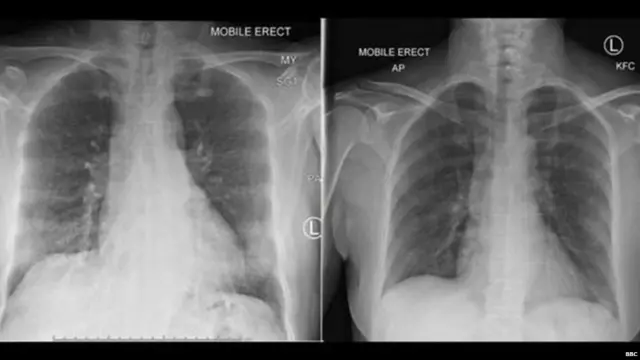

इन कोशिकाओं का पता एक संक्रमित महिला की जांच से किया गया. उन्हें मामूली-मध्यम संक्रमण था और उसे इसके अलावा दूसरी कोई भी बीमारी नहीं थी.

चीन के वुहान शहर की एक महिला को संक्रमण के बाद ऑस्ट्रेलिया के एक अस्पताल में भर्ती कराया गया था. भर्ती कराये जाने के 14 दिनों के भीतर वो पूरी तरह स्वस्थ हो गईं.

प्रोफ़ेसर केडज़िएर्स्का ने बीबीसी को बताया कि उनकी टीम ने इस महिला की विस्तृत जांच की. उनकी जांच के केंद्र में इस महिला का इम्यून सिस्टम था.

टीम ने अपनी जांच में यह पता लगाने की कोशिश की कि इस महिला का इम्यून सिस्टम कोरोना वायरस के संक्रमण पर किस तरह की प्रतिक्रिया करता है.

वो बताती हैं "जब महिला की स्थिति में सुधार आने लगा तो उसके खून के बहाव में कुछ विशिष्ट प्रकार की कोशिकाओं को देखा गया. ये कुछ उसी तरह की वही कोशिकाएं थीं जो इंफ़्लूएंज़ा के मरीज़ों में ठीक होने से पहले दिखाई देती हैं."